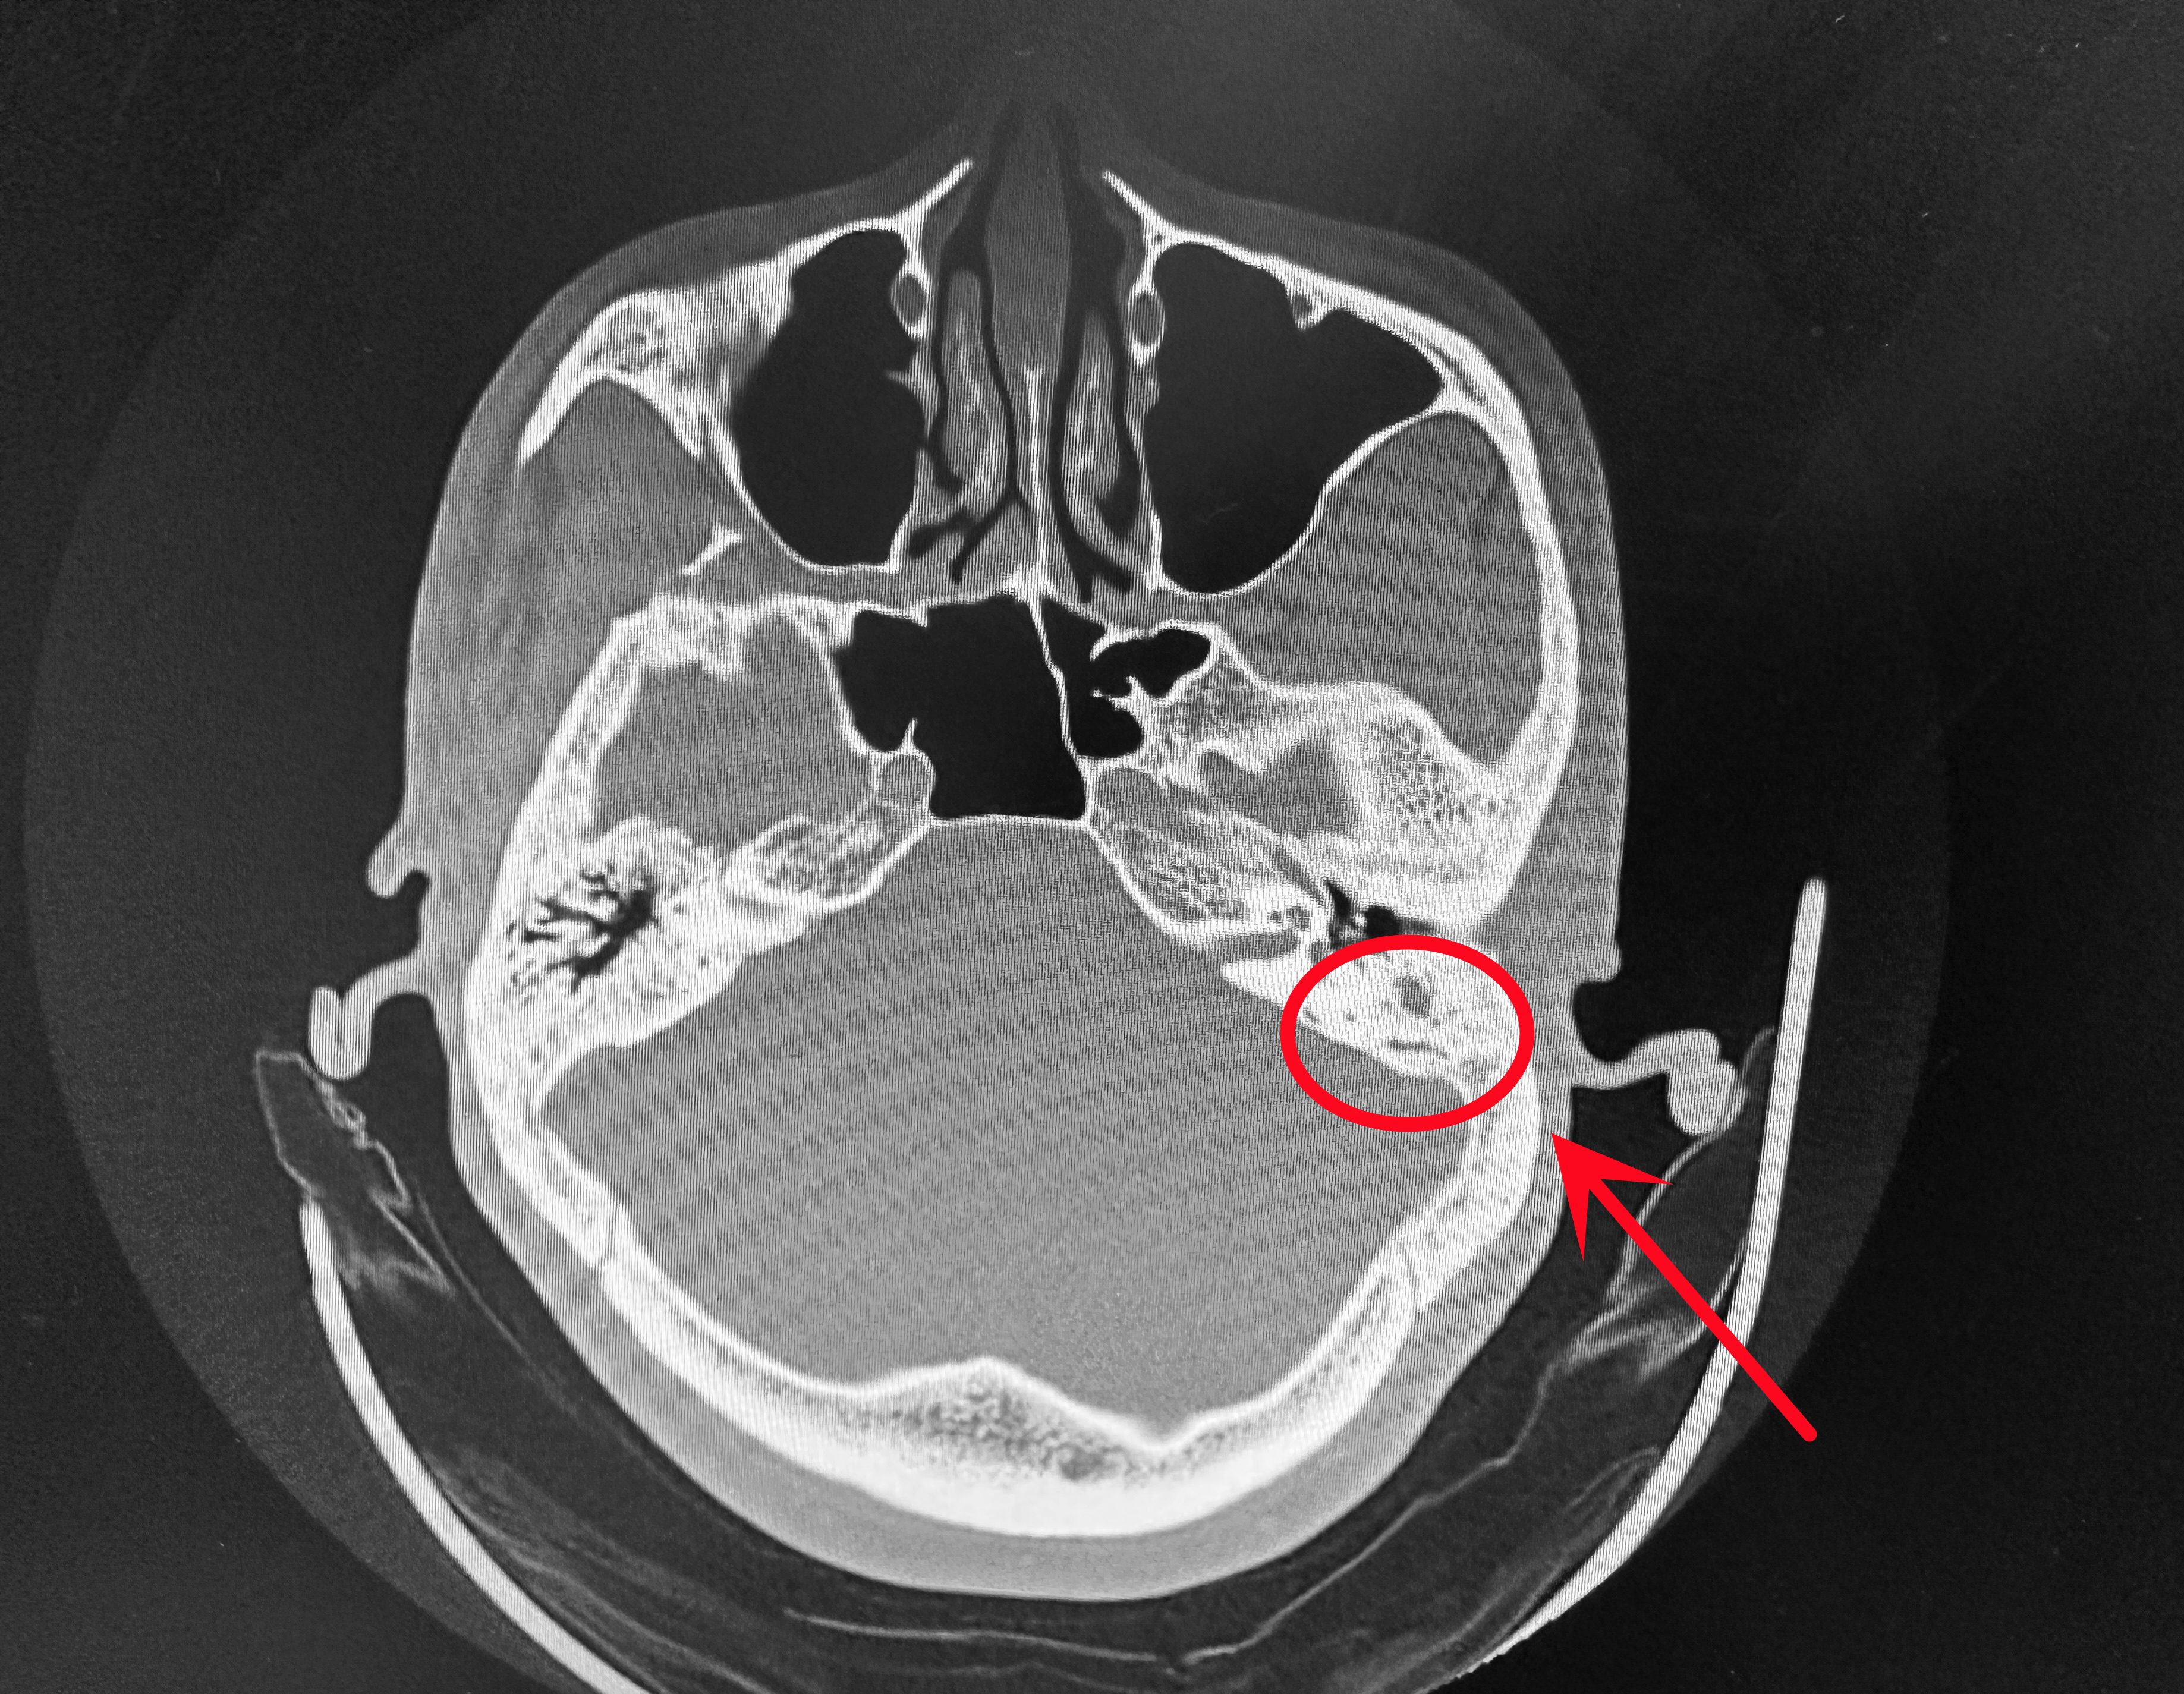

胆脂瘤型中耳炎是一种以非真性肿瘤形式存在的中耳疾病,其本质是外耳道鼓膜皮肤向中耳腔内异常增生形成的病变结构核心病理特征为角化上皮细胞堆积形成的“胆脂瘤囊”,该囊状结构具有持续扩张性,可破坏周围骨质其生长过程并非恶性增殖,但因长期机械压迫和酶解作用,对骨质的侵蚀能力极强,易突破中耳结构界限,向邻近区域蔓延。

胆脂瘤型中耳炎是中耳腔的良性病变,其病理特征为中耳腔黏膜上皮化生形成囊袋样结构,囊内充满脱落的上皮细胞角化物质及胆固醇结晶以下从病因症状诊断治疗及预防五个方面展开说明病因主要由感染鼓膜穿孔和咽鼓管功能障碍引发急性中耳炎未彻底治疗导致中耳腔持续感染,可能形成胆脂瘤鼓膜穿孔。